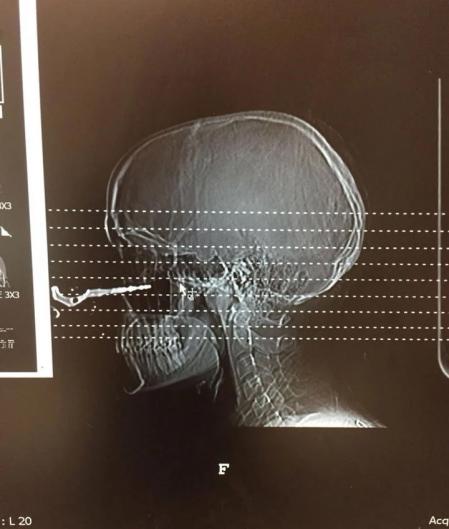

Los médicos que atendieron a la joven hicieron fotografías para dejar constancia del extraño suceso

Los amigos de Renée llamaron a una ambulancia y, tan pronto como llegó al hospital, le hicieron una tomografía computarizada y llamaron a un cirujano plástico para que le quitara la llave del coche y le cosiera la herida.

Al parecer, las pruebas revelaron que el objeto se había incrustado profundamente en su cavidad nasal, debajo del ojo, que por milímetros se salvó de ser perforado. “Había médicos que venían de diferentes departamentos para verlo porque no podían creerlo”, contó Lariviere mientras añadía que “Hice que uno de ellos viniera y pidiera tomar fotografías para poder mostrárselas a sus alumnos. Era un médico de la sala de emergencias, por lo que estaba tratando de mostrarles que cualquier cosa podía pasar”.